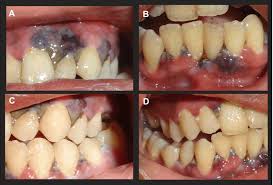

Treatment should include the alleviation ol the acute symptoms and the correction ol the underlying chronic gingival disease. If nug is left untreated it can progress to the more severe forms. Treatment is gentle debridement improved oral hygiene mouth rinses supportive care and if debridement must be delayed antibiotics. Sequela of single or multiple episodes of necrotizing ulcerative gingivitis nug signs. Characterized by necrosis of gingival tissues and loss of periodontal ligament and alveolar bone see fig.

It has an acute clinical presentation with the distinctive characteristics of rapid onset of interdental gingival necrosis gingival pain bleeding and halitosis. Acute necrotizing ulcerative gingivitis anug occurs most frequently in smokers and debilitated patients who are under stress. Treatment of acute necrotizing ulcerative gingivitis. Acute necrotizing ulcerative gingivitis anug has been generally considered as a gingivitis. Acute necrotizing ulcerative gingivitis definition acute necrotizing ulcerative gingivitis or anug is characterized as a plymicrobial infection of the patient s gums that normally leads to bleeding inflammation necrotic gum tissue and deep ulcerations.